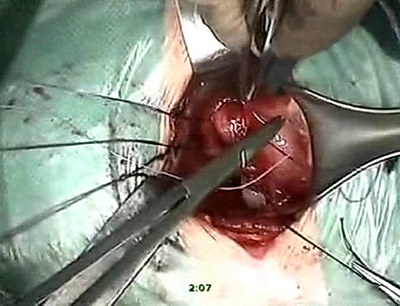

Мочеточники перекрёстно уложены в подслизистый тоннель между

устьями в области треугольника Льето. Выполнена резекция

мочеточников на протяжении 2 см и анастомоз со слизистой

мочевого пузыря викрилом 4/0 выше устьев мочеточников. Слизистая

мочевого пузыря ушита викрилом 4/0. Мочеточники интубированы.

Установлена цистостома. Стенка мочевого пузыря ушита двойным

непрерывным викриловым швом, цистостома фиксирована к мочевому

пузырю, дренажи-интубаторы выведены через контраппертуры

на переднюю брюшную стенку, фиксированы. В рану установлен

резиновый дренаж. Гемостаз. Сухо. Кровопотеря - 100мл. Рана

ушита послойно, косметический шов на кожу. Обработка йодопироном,

асептическая наклейка.